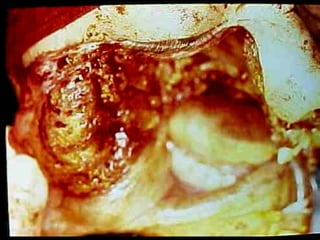

Mucormicosis

ntroducción.

Con este término, nos referimos a un grupo de micosis causadas por hongos

del orden Mucorales. La mayoría de los casos se presenta en personas con

factores de oportunismo severos como diabetes mellitus descompensada,

leucemia, o cáncer. Son infecciones graves que pueden causar la muerte; las

variedades clínicas más frecuentes son: rinocerebral, pulmonar, digestiva y

cutánea primaria. Las infecciones causadas por hongos del orden Mucorales,

generalmente se adquieren por vía respiratoria ya que las esporas de los

hongos se encuentran en el ambiente, aunque en las formas cutáneas

primarias, la infección se adquiere por solución de continuidad.

La paciente falleció a las 24 horas de internamiento por trombosis del seno